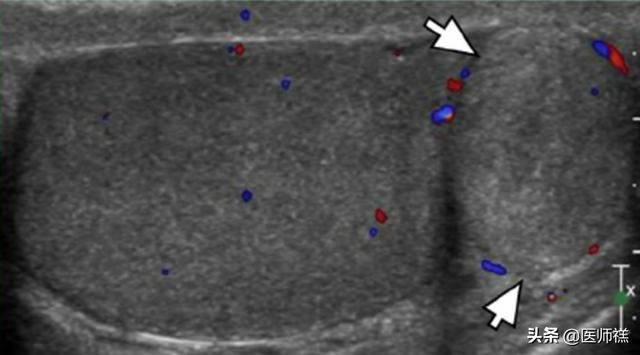

Si cela se produit.La grande majorité d'entre eux sont des lipomes.Toutefois, il ne s'agit que d'un simple diagnostic par palpation et inspection visuelle, et le diagnostic spécifique doit être combiné avec les résultats de l'examen clinique et l'analyse des antécédents médicaux du patient afin de porter un jugement correct. Par exemple, l'échographie couleur peut être utilisée pour déterminer la limite de la masse, la membrane dorsale, et pour observer les vaisseaux sanguins et les nerfs autour de la masse.

Lipome à l'échographie couleur

Bien que les lipomes soient des tumeurs bénignes, nous devons déterminer s'ils sont causés par d'autres tumeurs malignes présentant les mêmes modifications.Si la masse est entourée d'une réserve de sang, accumulant des nerfs et des vaisseaux sanguins importants, il faut craindre qu'il s'agisse d'une tumeur maligne. L'inspection visuelle, la palpation, l'observation par ultrasons et même l'analyse histopathologique de la composition de la tumeur nous permettront de poser un diagnostic définitif.En effet, même dans le cas de maladies bénignes, il convient d'être très rigoureux et de ne pas tirer de conclusions hâtives, faute de quoi le risque d'erreur de diagnostic est élevé, ce qui peut être un fléau pour notre santé.